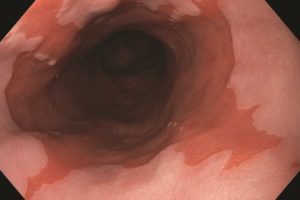

Τι προκαλεί τον οισοφάγο Barrett

Ο οισοφάγος Barrett είναι μια μη φυσιολογική μεταπλασία στο οισοφαγικό επιθήλιο (παρόμοιο με τον εντερικό ιστό). Ο οισοφάγος Barrett μπορεί να προχωρήσει σε οισοφαγικό αδενοκαρκίνωμα, που είναι σπάνιος τύπος καρκίνου.